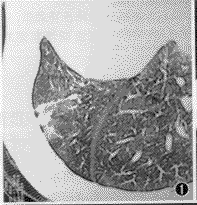

CT扫描,12例均有明显异常病灶显示。本组病例胸部CT表现包括:(1)小结节病灶 10例,结节影直径均在1 cm以下(范围0.5~1.0 cm),位居肺野外带胸膜下部(图1),其中8例小结节影周缘可见磨玻璃样密度的晕圈,即月晕征(图2,3)。(2)小斑片局灶性磨玻璃样密度影,在肺野外带浸润(图4),斑片与正常肺临界缘呈“小三角形”改变7例,部分在肺尖部散在,形似浸润型结核(图5)。(3)外带支气管血管束呈局灶性“Y”形增粗3例(图6)。上述小结节影、小斑片淡薄影均在两肺周边区域呈多灶性散在分布,没有大叶融合倾向。全组病例纵隔、肺门部未见肿大淋巴结。

图1 右肺中叶胸膜下区小结节灶,与之连接的支气管血管束增粗